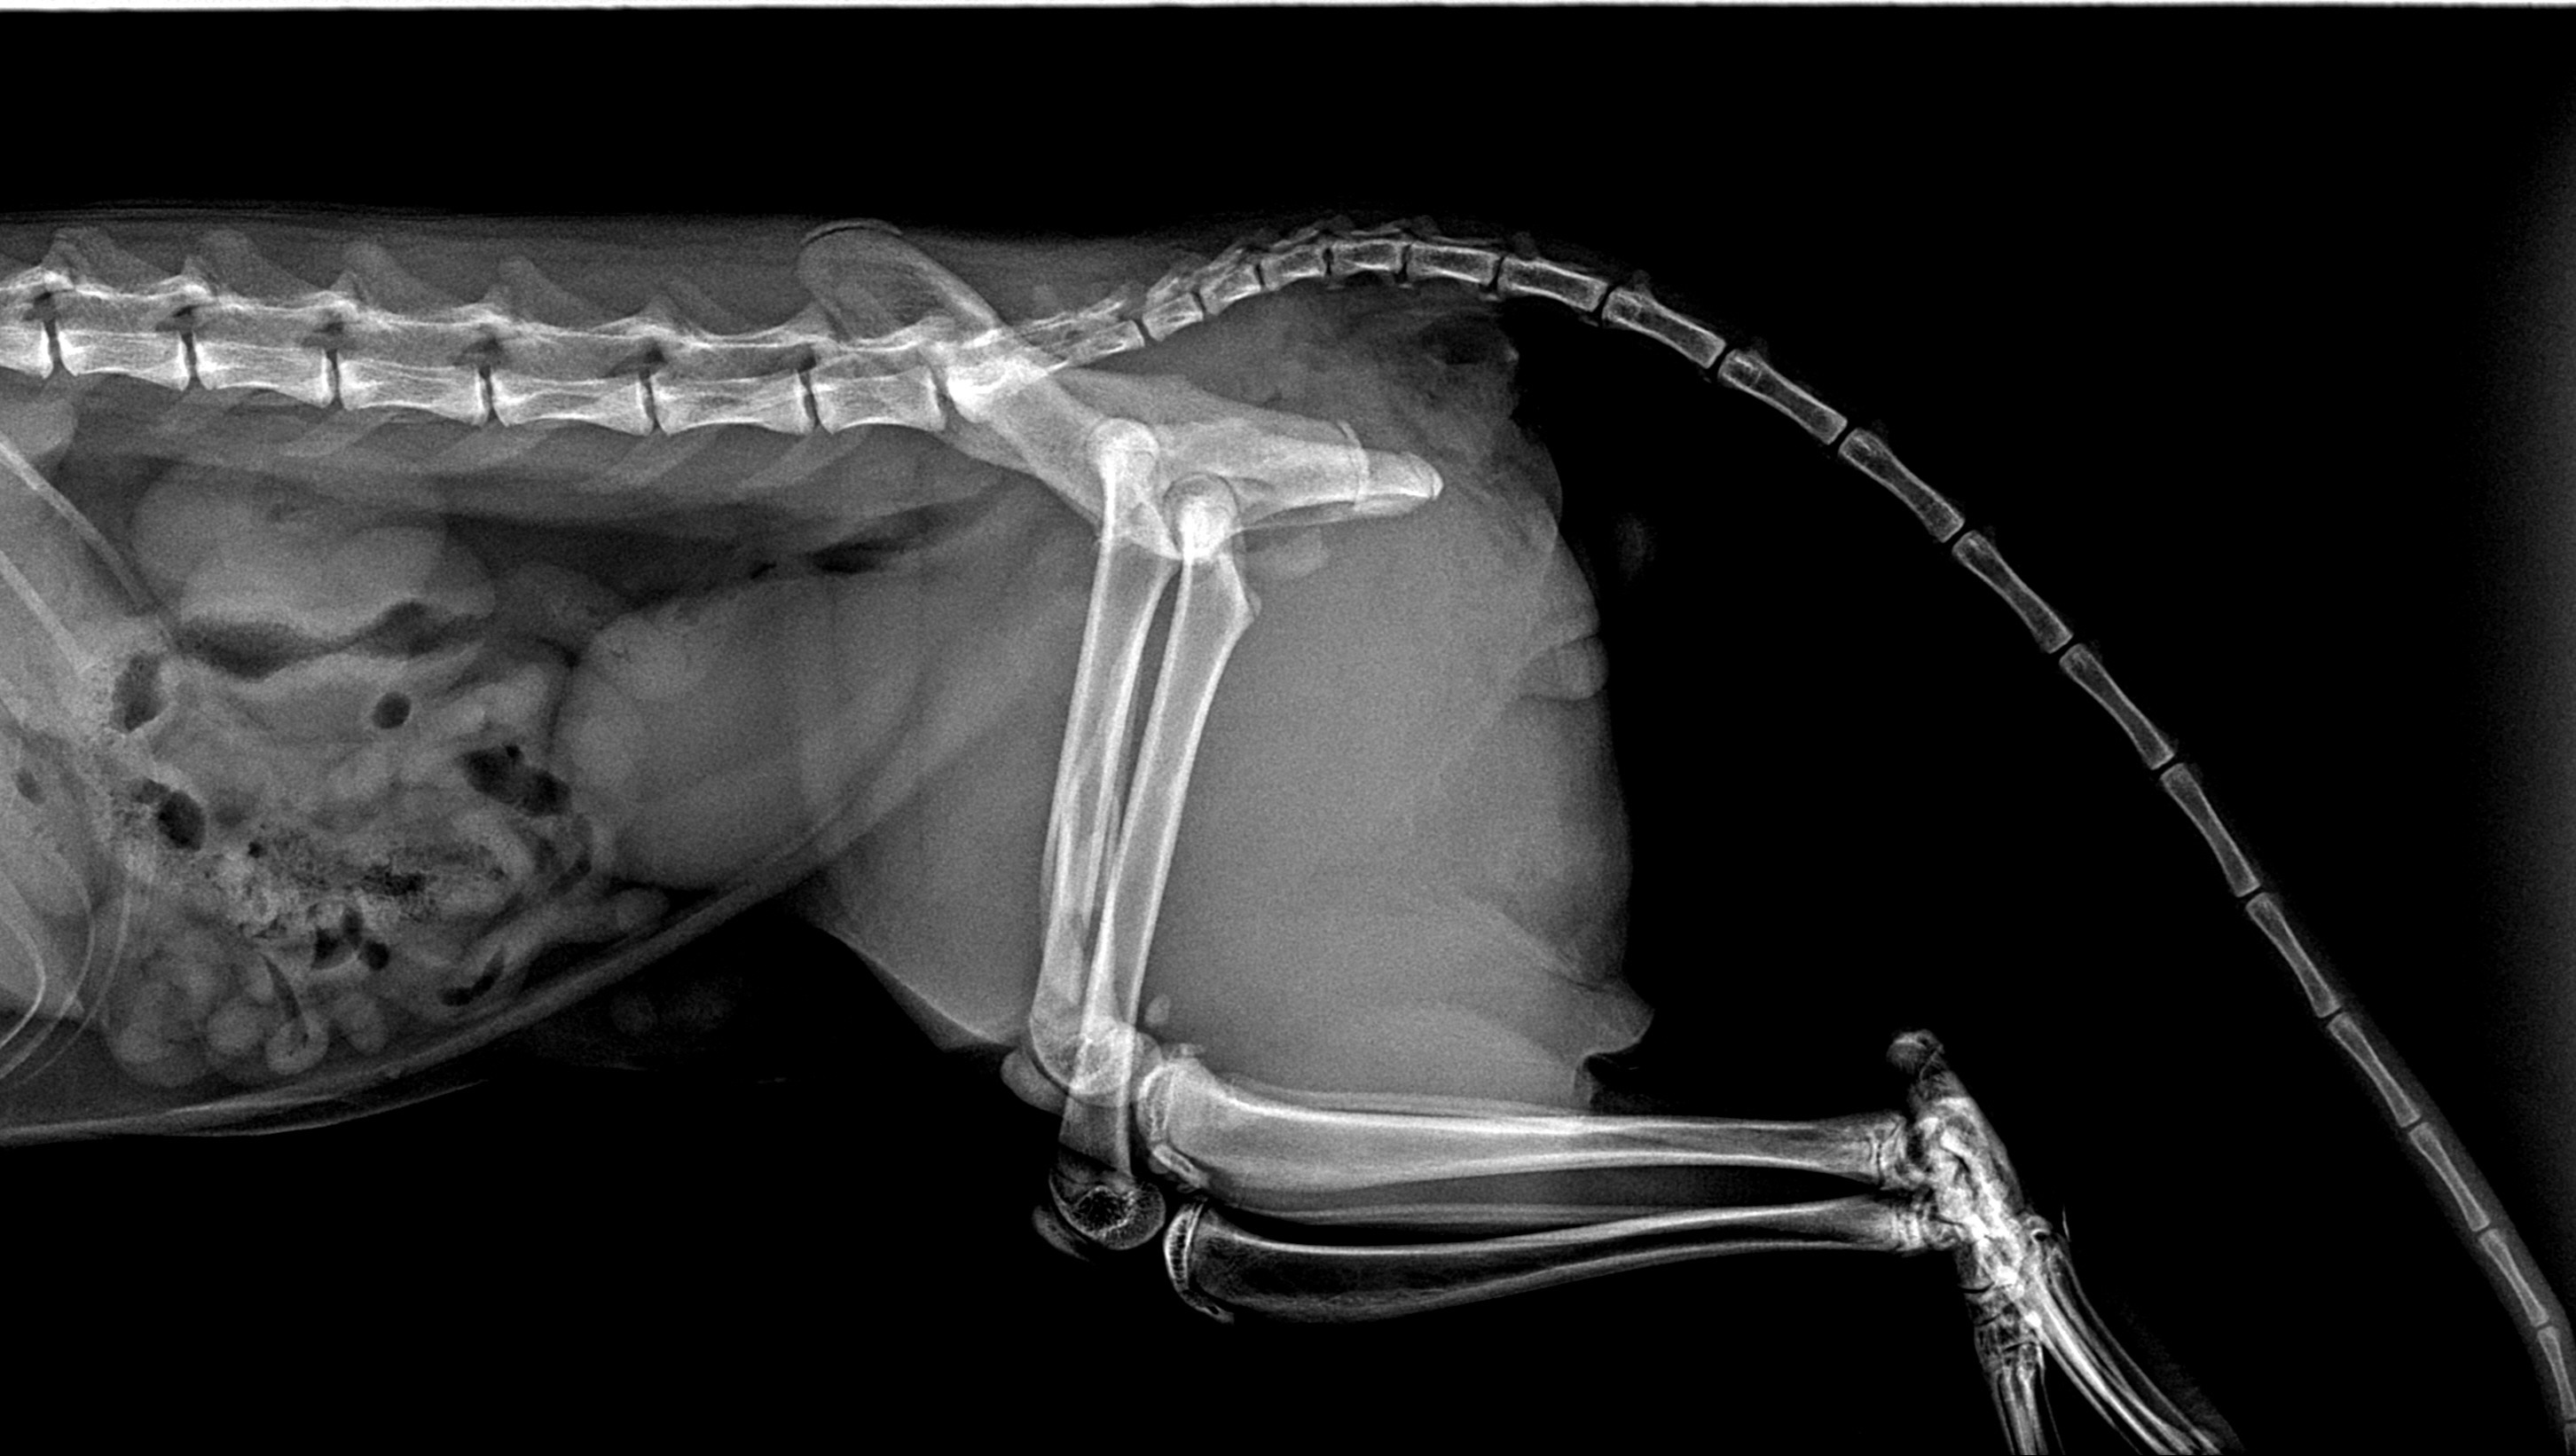

Our sweet angel of a kitten is seriously injured. His name is Nugget, he is an orange tabby and he is 7 months old. We found out that his pelvis was snapped in half, and his femur was shattered. He was likely hit by a car or was trapped by an animal that pulled his leg. He is going to need surgery to walk again, but we can't afford to save him. We want to help him as much as we can, but are struggling to support his healing journey. Please help bring our baby home safely!

His checkups, bloodwork, x-rays, and prognosis have come out to a total of 1,620, and his surgery was quoted for 3,800.